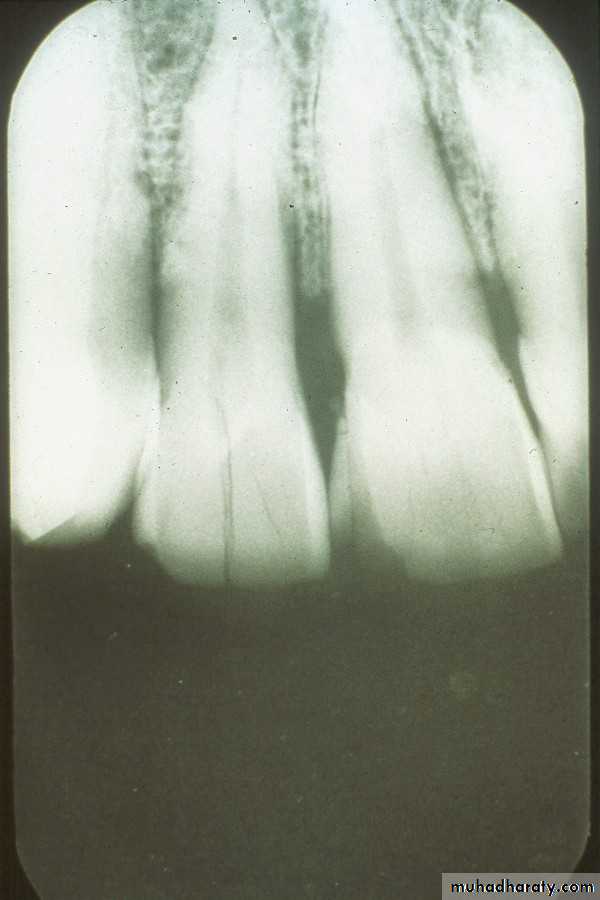

In the paralleling technique( the illustration above left), the film is positioned in the mouth so that the long axis of the film and the long axis of the tooth are parallel.

In the illustration above right, the film is placed straight up and down and is not parallel; the patient is unable to close completely on the biteblock and the apices of the teeth would not appear on the film.

correct

incorrect